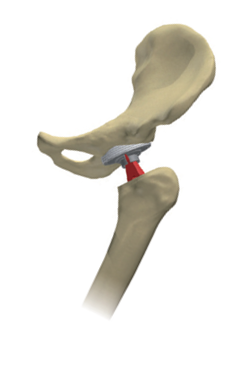

Question

Which design philosophy best describes this diagram?

Answer

• Composite beam

• Polished Taper

• Hybrid